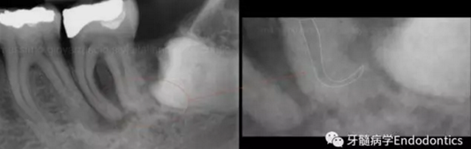

圖2.疏通根管冠方2/3后,使用次氯酸鈉溶液沖洗根管,且可以使用手用器械、GG鉆(刷洗動作)、旋轉鎳鈦成形銼預敞根管。當冠方2/3進行了合適的預備且充滿沖洗液后,接著進行根尖1/3的探查以收集信息。使用小的手用銼(8號或10號K銼)疏通根管的剩余部分,確認建立了流暢的、無阻礙的、平滑的到達根尖止點的引導通道。

圖3.存在細小狹長、可能多維的復雜根管解剖時,使用10號K銼不可能立即疏通根管到達根尖止點。隨后醫(yī)生應嘗試使用更小的銼探查以達到根尖。但是,通常不需要使用6號和8號K銼對到達根尖的引導通道進行擴大,除非是特別困難的病例。